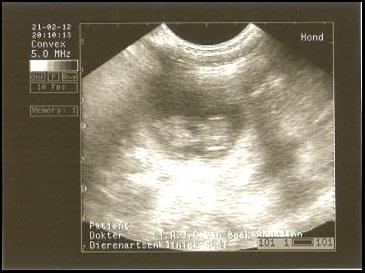

ER IS NIEUWS! Wisper is gedekt door haar liefde Bikkel (Boef) op 21/22 januari. We hopen in de lente 2012 de pups van het mooie paar te verwelkomen! Op 21 februari is er een echo gemaakt en ja hoor….. WISPER IS DRACHTIG! |